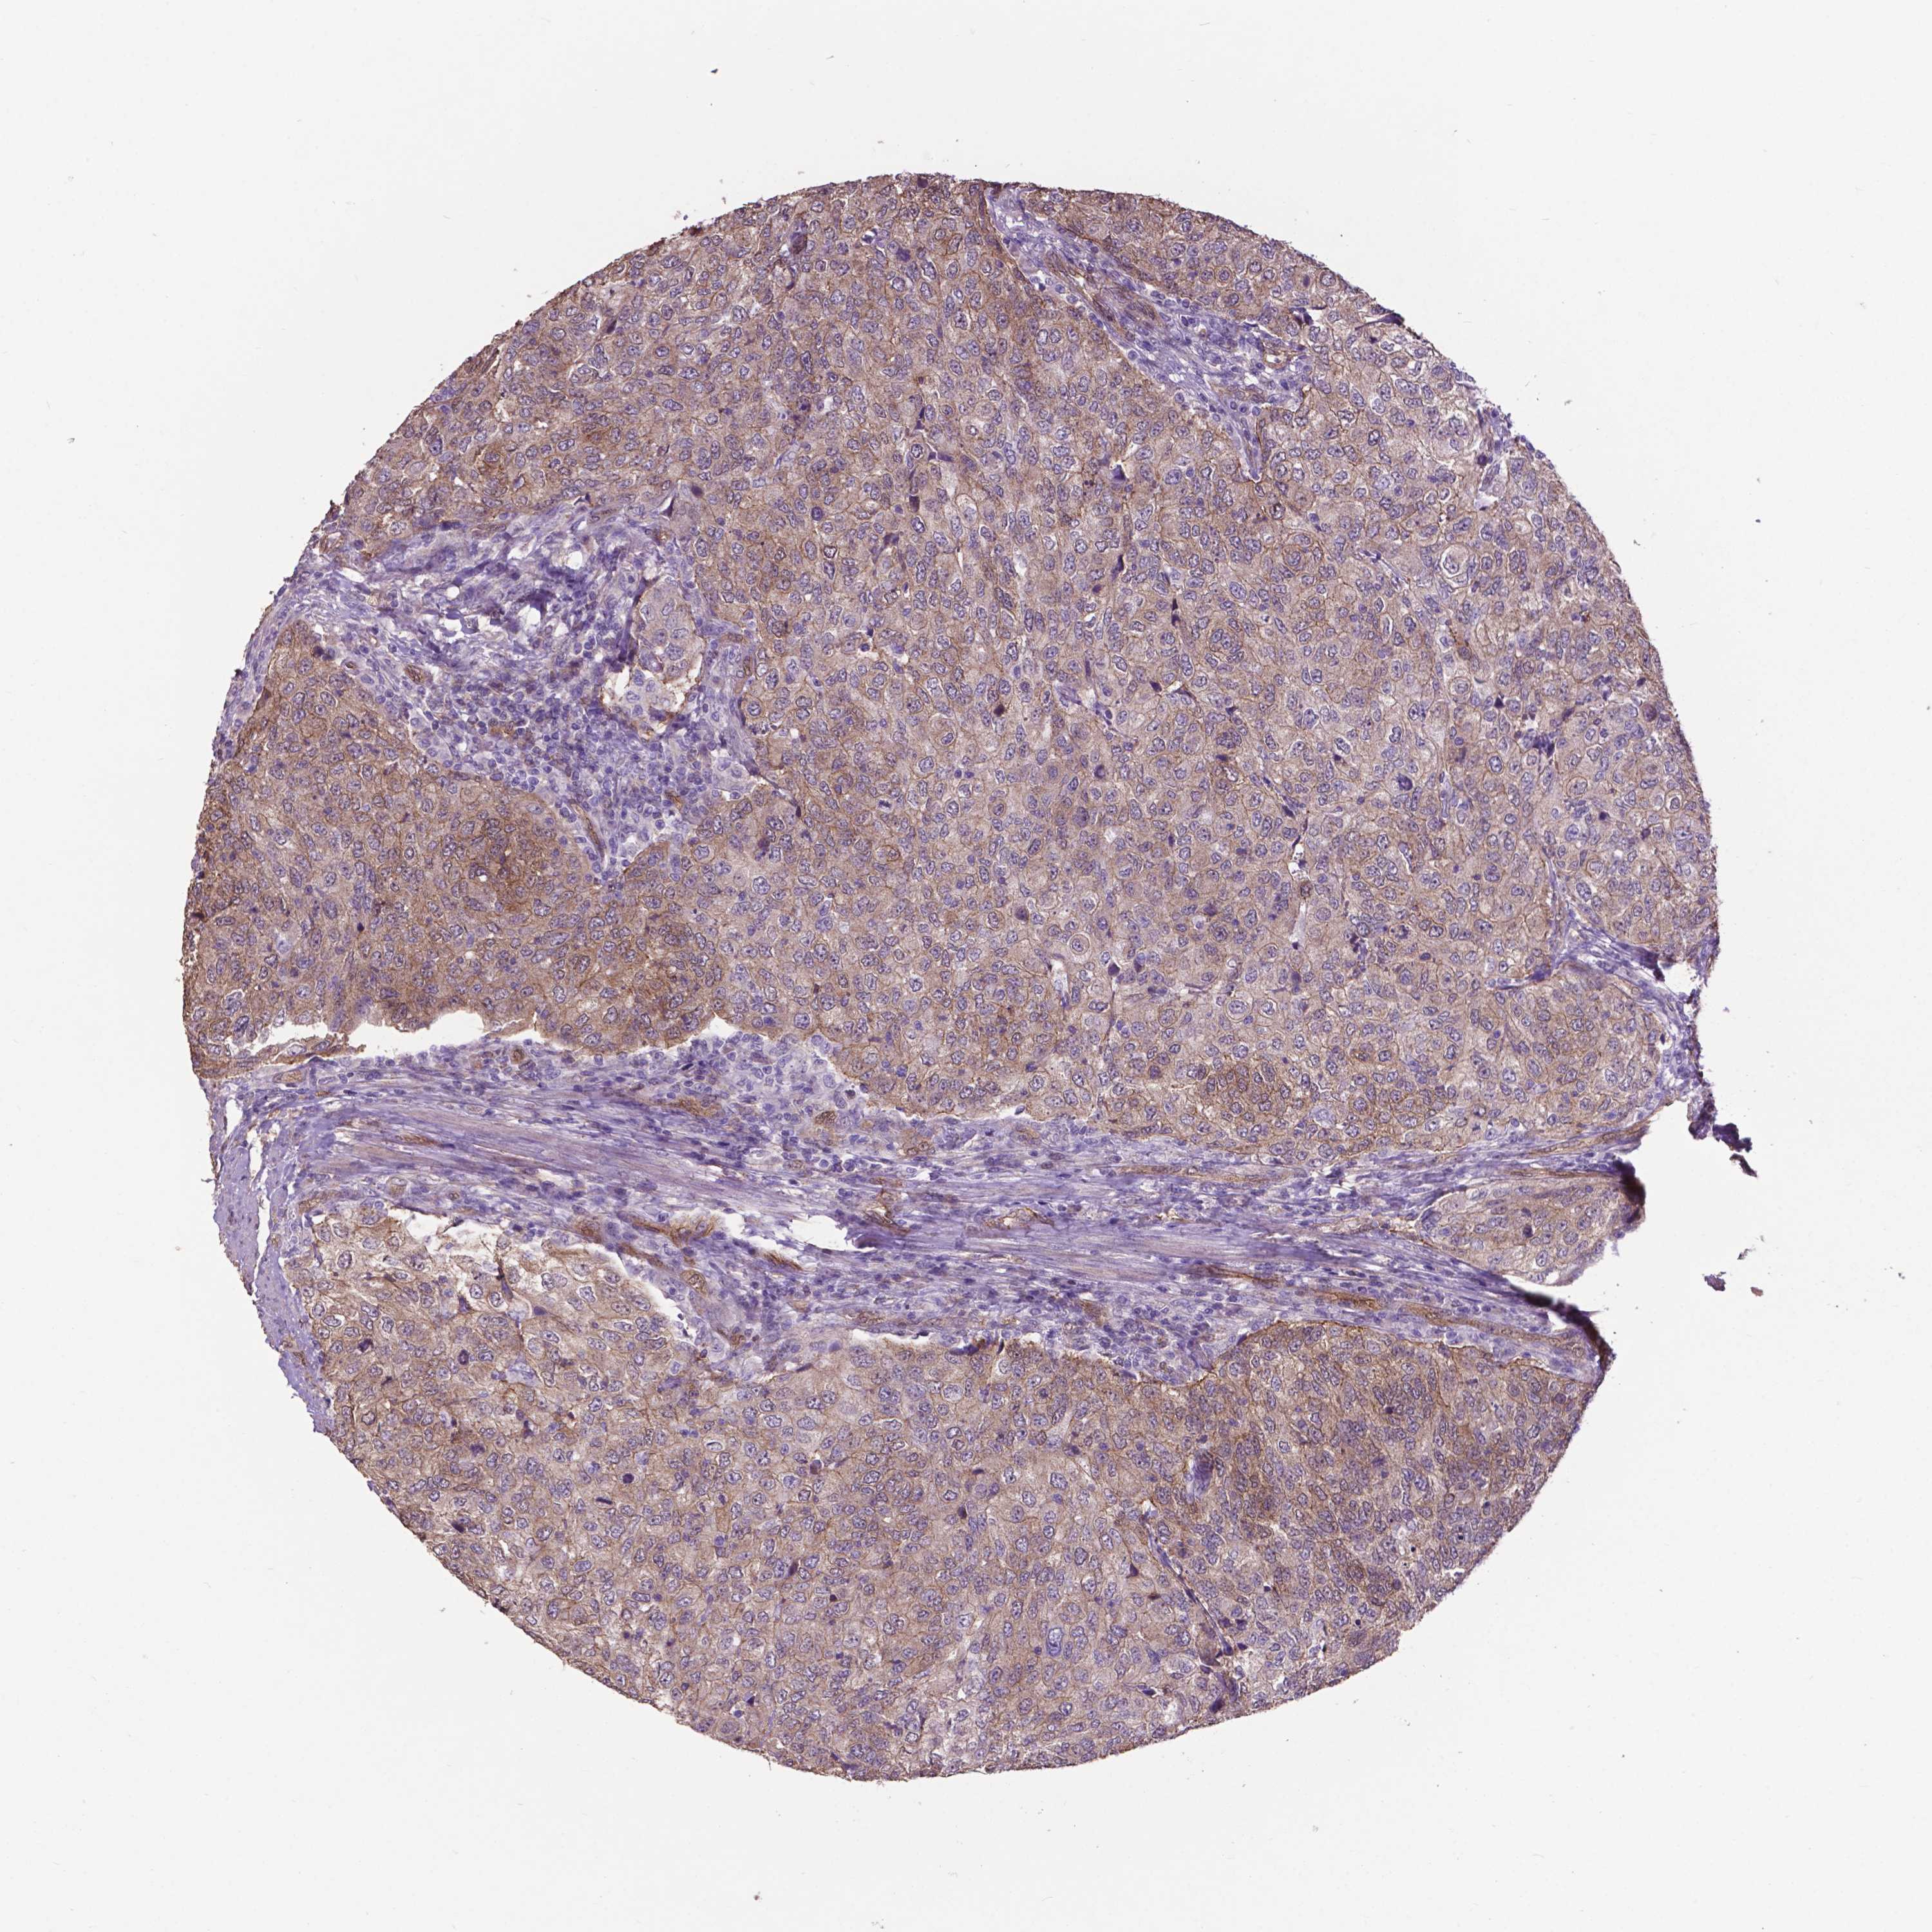

UROTHELIAL CANCER - Protein expressioni

A mouse-over function shows sample information and annotation data. Click on an image to view it in a full screen mode. Samples can be filtered based on level of antibody staining by selecting one or several of the following categories: high, medium, low and not detected. The assay and annotation is described here.

Antibody stainingi

Antibody staining in the annotated cell types in the current human tissue is reported as not detected, low, medium, or high, based on conventional immunohistochemistry profiling in selected tissues. This score is based on the combination of the staining intensity and fraction of stained cells.

Each image is clickable and will lead to virtual microscopy that enables deeper exploration of all samples and also displays staining intensity scores, fraction scores and subcellular localization as well as patient and tissue information for each sample.

Antibody HPA017010

Antibody CAB072838

Staining

High

Medium

Low

Not detected

Intensity

Strong

Moderate

Weak

Negative

Quantity

>75%

75%-25%

<25%

None

Location

Nuclear

Cytoplasmic/membranous

Cytoplasmic/membranous,nuclear

Urothelial carcinoma, High grade